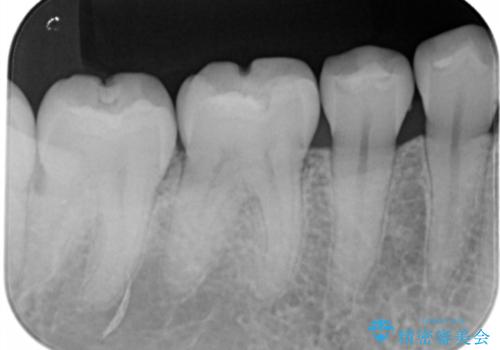

- 右下6・7番の咬合面に詰められた保険材料が劣化していたので、審美性・切削量を考慮しセラミックインレー治療を選択しました。

劣化した保険材料・虫歯を全て除去した上で形成しています。